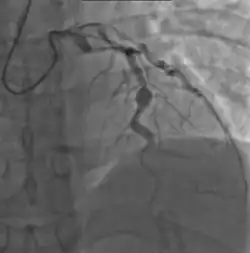

Heart complications are the most important aspect of Kawasaki disease, which is the leading cause of heart disease acquired in childhood in the United States and Japan.[32] In developed nations, it appears to have replaced acute rheumatic fever as the most common cause of acquired heart disease in children.[16] Coronary artery aneurysms occur as a sequela of the vasculitis in 20–25% of untreated children.[53] It is first detected at a mean of 10 days of illness and the peak frequency of coronary artery dilation or aneurysms occurs within four weeks of onset.[49] Aneurysms are classified into small (internal diameter of vessel wall <5 mm), medium (diameter ranging from 5–8 mm), and giant (diameter > 8 mm).[32] Saccular and fusiform aneurysms usually develop between 18 and 25 days after the onset of illness.[16]

Even when treated with high-dose IVIG regimens within the first 10 days of illness, 5% of children with Kawasaki disease develop at the least transient coronary artery dilation and 1% develop giant aneurysms.[54][55][56] Death can occur either due to myocardial infarction secondary to blood clot formation in a coronary artery aneurysm or to rupture of a large coronary artery aneurysm. Death is most common two to 12 weeks after the onset of illness.[16]

Many risk factors predicting coronary artery aneurysms have been identified,[22] including persistent fever after IVIG therapy,[57][58] low hemoglobin concentrations, low albumin concentrations, high white-blood-cell count, high band count, high CRP concentrations, male sex, and age less than one year.[59] Coronary artery lesions resulting from Kawasaki disease change dynamically with time.[4] Resolution one to two years after the onset of the disease has been observed in half of vessels with coronary aneurysms.[60][61] Narrowing of the coronary artery, which occurs as a result of the healing process of the vessel wall, often leads to significant obstruction of the blood vessel and the heart not receiving enough blood and oxygen.[60] This can eventually lead to heart muscle tissue death, i.e., myocardial infarction (MI).[60]

- Angiography was historically used to detect coronary artery aneurysms, and remains the gold standard for their detection, but is rarely used today unless coronary artery aneurysms have already been detected by echocardiography.